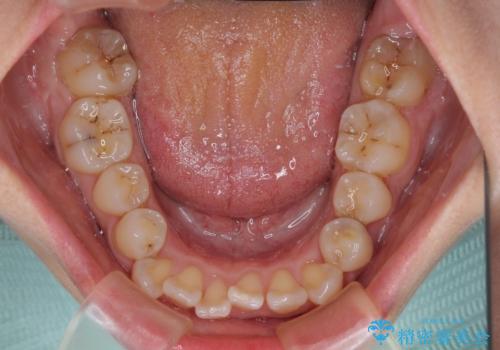

- 前歯のデコボコを治したいとのことで来院された患者様です。

上下顎ともに歯列全体の後方移動とIPR(歯と歯の間を削る)によってデコボコが解消するように設計し、インビザラインにより治療を行うこととしました。

下顎前歯は後戻りを起こしやすいため、舌側を細いワイヤーで固定し、マウスピース型リテーナーで保定を行うこととしました。